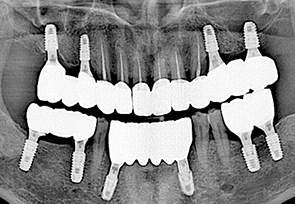

• before

• after